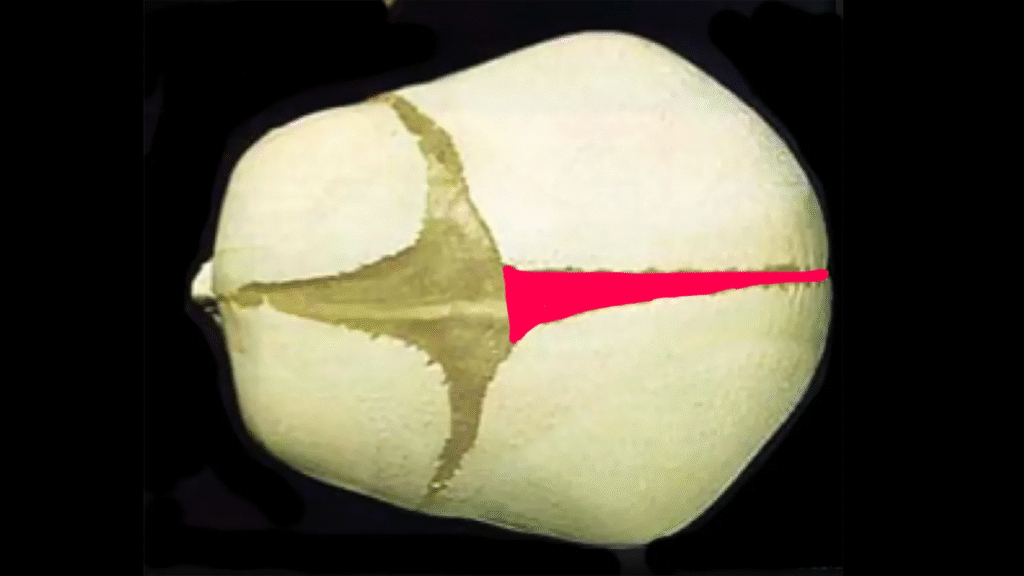

At El Paso Craniofacial Team, the primary treatment for craniosynostosis is surgery. First performed in the late 1800s, surgical approaches have continued to evolve and improve. The two main approaches are Calvarial Vault Remodel (CVR) and endoscopic-assisted surgery, with each tailored to the child’s age, the affected suture, and the severity of the condition.